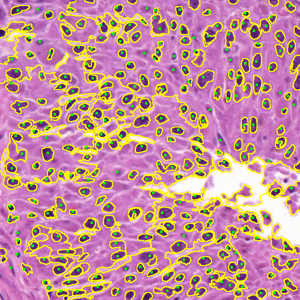

Figure 9 shows the segmentation results for the first hematoxylin and eosin (H&E)–stained image from Dataset 1 (see Fig. LABEL:fig_sub:he1_image). Initial level sets and superpixels are shown in Figs. LABEL:fig_sub:he1_in1_zz-LABEL:fig_sub:he1_in_SP: AR and ZZ used two distinct level sets for nuclei (S1) and cytoplasm (S2) (Figs. LABEL:fig_sub:he1_in1_zz-LABEL:fig_sub:he1_in2_zz), while SP and SMST (Fig. LABEL:fig_sub:he1_in_SP) used the same set of 4000 Power-SLIC superpixels in the same color space (red channel for S1, remaining channels for S2). SAM does not allow separate-channel segmentation; its combined S1/S2 result is shown in Fig. LABEL:fig_sub:he1_out_SAM. Figures LABEL:fig_sub:he1_out1_AR-LABEL:fig_sub:he1_out1_SP display S1 results for AR, ZZ, SMST, and SP, and Figs. LABEL:fig_sub:he1_out2_AR-LABEL:fig_sub:he1_out2_SP show the corresponding S2 results.

AR seemed highly sensitive to initialization, segmenting mainly regions near seed points and requiring seeds in nearly all connected foreground components for satisfactory performance. ZZ segmented a wider range of objects from fewer seeds but incorrectly included nuclei in cytoplasm segmentation, failing to capture white regions and introducing spurious tissue. SAM automatically detected many nuclei and some cytoplasm but merged all structures into a single segmentation, limiting its practical utility here. SMST was the fastest but failed to recover large homogeneous regions, such as the background, and frequently fragmented them due to its variance-based metric. In contrast, SP yielded the most accurate results on both S1 and S2, with clear background separation and precise boundary delineation.

Figure 9: Unsupervised segmentation of the image in Fig. LABEL:fig_sub:he1_image for two structures: purple cells (S1) and white cytoplasm (S2). Initializations via level sets (LS) for AR and ZZ are shown in (a, b); 4000 superpixels for SMST and SP in (c) (red channel for S1, remaining channels for S2). SAM does not allow separate-channel segmentation; its overall output is in (d). Results for S1 are in (e–h) and for S2 in (i–l). Computation times (S1/S2, in seconds): AR 829.51/570.32, ZZ 4304.50/4470.56, SMST 0.38/0.38, SP 5.98/4.26; superpixels in (c) computed in 0.17s, SAM in (d) in 7.42s.